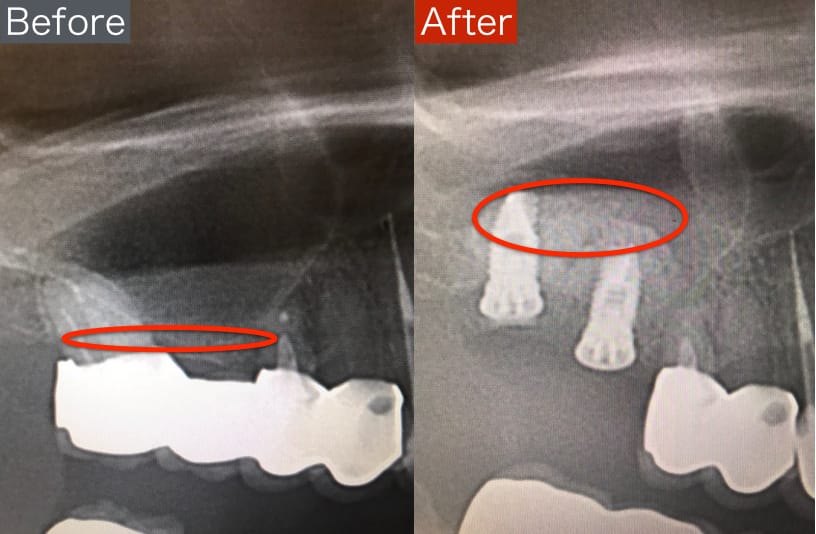

前医でインプラントの埋入角度が悪く、インプラント周囲炎になってしまった患者様の症例です。

インプラントが虫歯になることはありませんが、インプラント周囲炎というインプラントの歯周病にはなります。

インプラント周囲炎の主な原因は汚れ(菌)と力です。このように斜めに埋入されているインプラントは、真っ直ぐ埋入されているものに比べて汚れも溜まりやすく、噛む力も斜めにかかってしまうため、インプラント周囲炎になるリスクが大幅に高くなります。

この患者様は内側の骨が大幅に溶けてしまっていたので、前のインプラントを撤去して、骨を再生させると同時にインプラントを正しい位置と角度で埋入し直しました。溶けてしまっていた骨が治っていることもレントゲンでご確認いただけるかと思います。

インプラントは「どこの位置にどのような角度で入れるか」によって、一生使い続けられるかどうかの期待値が大きく異なります。値段だけを基準にクリニックを決めるのではなく、信用できる歯医医師と治療を進めることをお勧めします。